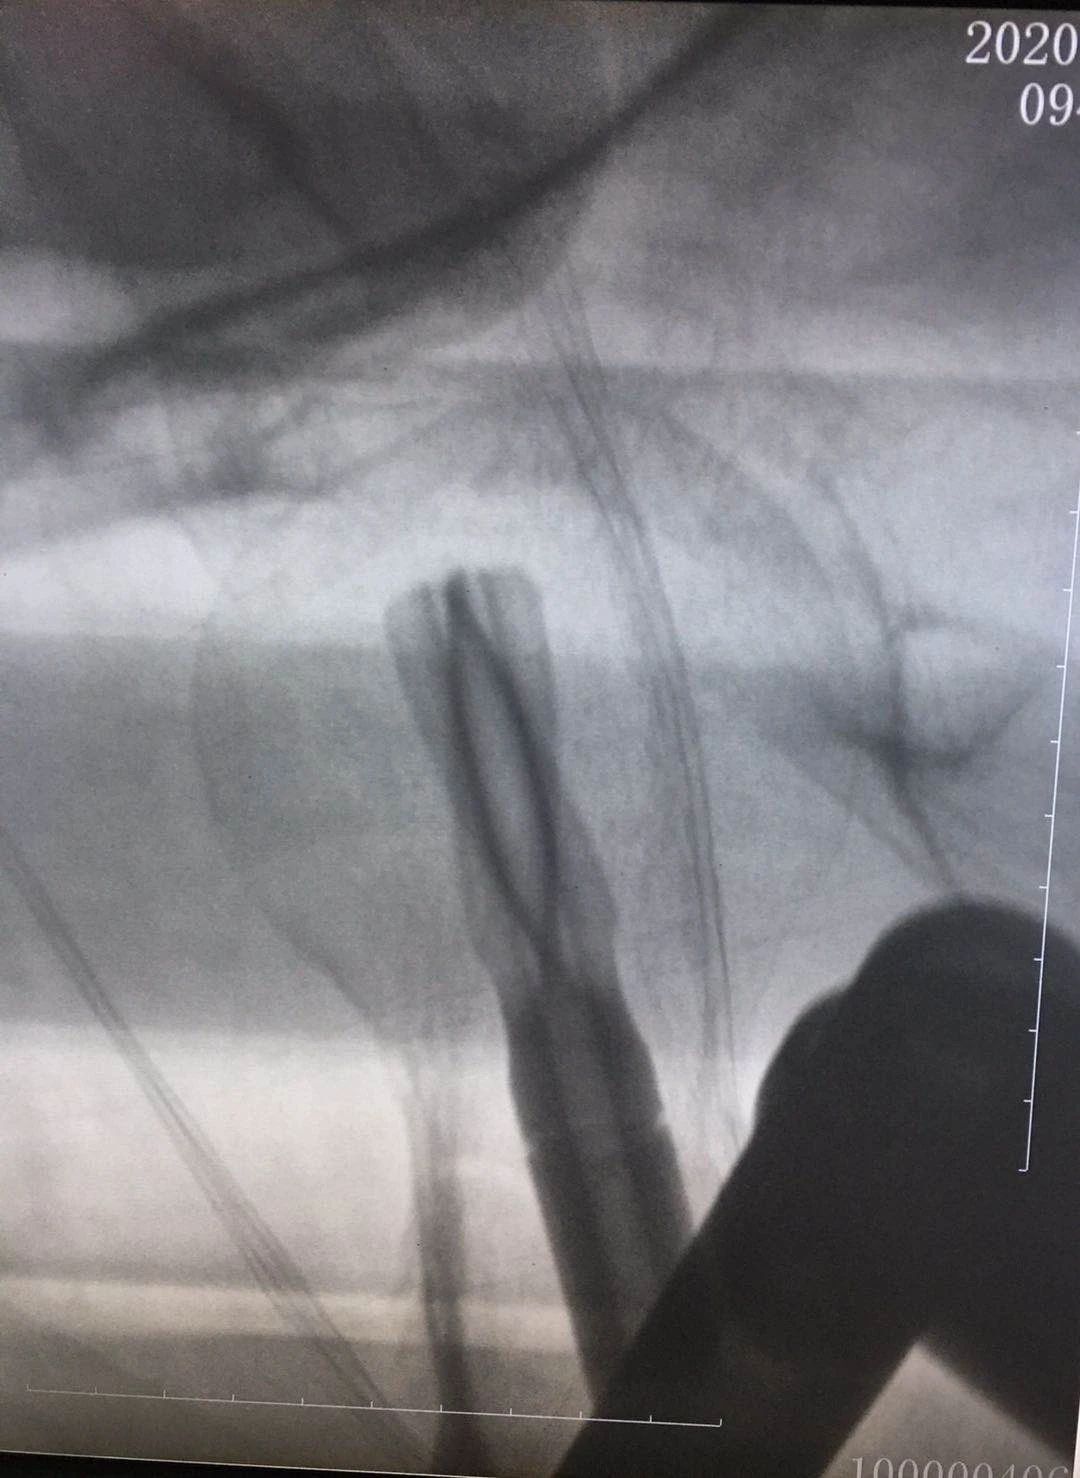

术后影像: